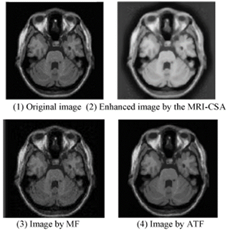

Otro caso de aplicación en el campo de la medicina es el presentado por los autores Gong, Tiantian, Lei Pei y Zixing (Gong et al. 2016) en donde se establece el problema de la estandarización de la lecturas de imágenes de resonancia magnética. En este trabajo se presenta el desarrollo de un algoritmo basado en la técnica de selección clonar del sistema inmunológico artificial modificado para mejorarlas imágenes. Los autores presentan como metodología de solución:

· Usar números reales para cifrar los anticuerpos de esta forma eliminar el cálculo de codificación en diferentes espacios numéricos.

· Limitar el campo de mutación en función de un radio entorno al clon original y su clon más lejano, evitando la dispersión de anticuerpos.

· Presentar un algoritmo en donde los anticuerpos forman vectores en un espacio de trabajo, a los cuales se les aplica una distribución gaussiana, uniforme y caótica para los procesos de mutación y de clonación, obligando al sistema a realizar una búsqueda global de soluciones.

En la figura 12 se observa el resultado en el filtrado y la correspondiente mejora de la imagen.

Los resultados presentan que el trabajo propuesto es más eficiente que los métodos de filtrado medio y filtro adaptativo, porque permite una mejor distribución del histograma de la imagen lo que permite detallar los elementos con mayor precisión.